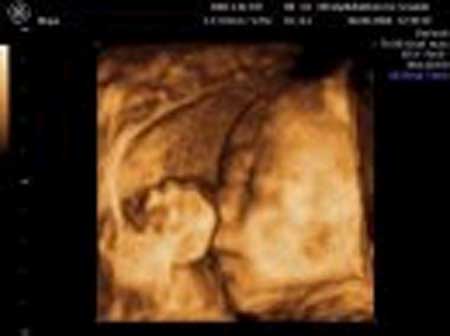

3D scanning – se baby i maven under graviditeten

3d scanning uge 26

3d scanning – uge 26